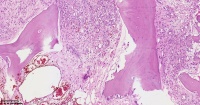

请教老师们这些巨细胞有什么临床意义?

性别

女

年龄

61岁

临床诊断

股骨头骨折

一般病史

标本名称

股骨头组织

大体所见

股骨头骨折处组织

多核吞噬细胞,有纤维素性坏死

是一种反应性改变。